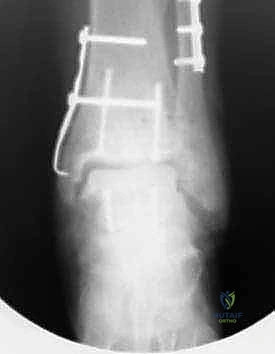

صور إضافية من داخل غرفة العمليات والخطوات الجراحية

ندرك أهمية توثيق الخطوات الجراحية لطلاب الطب والمرضى الراغبين في فهم دقة الإجراء. هذه الصور توضح مراحل زراعة وتثبيت الطعم العظمي الغضروفي بدقة متناهية تحت إشراف أ.د. محمد هطيف.